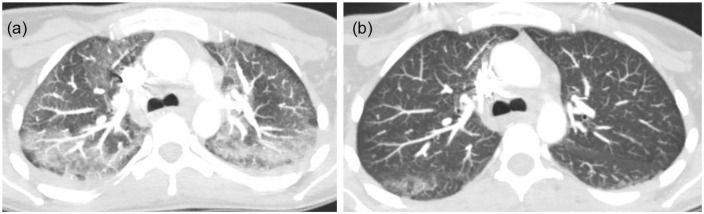

She returned to the emergency room the following day with progressively worsening shortness of breath. Her RR was 24 breaths per minute and saturating 84% on room air. Computed tomography angiogram (CTA) of the chest with and without contrast revealed bilateral patchy ground glass opacities within the bronchovascular distribution (Figure 1). The patient’s clinical condition deteriorated over the next 12 hours requiring high-flow oxygen and repeat imaging showed worsening bilateral pulmonary opacities. On further questioning, the patient admits to smoking marijuana, which she switched to vaping with CBD/THC oil 2 months prior to this presentation, which she bought off the street. She never smoked cigarettes. She denied having any pets, recent travel history, or exposure to any sick contacts. Laboratory workup was significant for leukocytosis, elevated erythrocyte sedimentation rate (ESR), C-reactive protein (CRP), procalcitonin, and urine drug screen was positive for cannabinoids/THC (Table 1). Airway examination was normal on bronchoscopy and bronchoalveolar lavage (BAL) gram stain showed mixed respiratory flora and cultures were negative bacterial, fungal, and viral pathogens. BAL differential showed 5% neutrophils, 10% lymphocytes, and 85% macrophages. Antibiotics were escalated to ceftriaxone and azithromycin for 5 days. She also received methylprednisone 60 mg daily × 3 days, then changed to oral prednisone 40 mg daily with a tapering course of 10 mg per week over a 4-week period. A presumptive diagnosis of VALI secondary to vaping CBD/THC was made as the patient responded very well to the steroids. Her symptoms significantly improved and was discharged home 7 days later without the need for supplemental oxygen.

A 34-year-old Caucasian female waitress at a local restaurant presented with complaints of worsening dyspnea, productive cough with yellow phlegm, nausea, vomiting, generalized weakness, and diarrhea for 2 weeks duration. She was prescribed azithromycin 10 days prior to this presentation without any improvement in her symptoms. She denied any sick contacts or travel abroad. She is a current cigarette smoker and also started vaping CBD/THC oil a year ago. She admits vaping CBD/THC oil bought from a local dispensary 2 days prior to her symptom initiation. On physical examination, the patient was in respiratory distress with vital signs of temperature 100.8 °F, HR 136 beats per minute, BP 123/88 mm Hg, RR 22 breaths per minute, and oxygen saturation of 88% on room air. Physical examination was significant for decreased breath sounds throughout the lung fields. Laboratory workup was significant for leukocytosis, elevated ESR, CRP, and urine drug screen was positive for cannabinoids/THC (Table 1). Extensive infectious workup including sputum studies urine and serum studies were negative (Table 1). CXR showed bilateral interstitial infiltrates and CTA of the chest with and without contrast confirmed bilateral upper lobe ground glass patchy infiltrates (Figure 5(a)). She was diagnosed with acute hypoxic respiratory failure likely from VALI secondary to vaping CBD/THC oil. The patient was started on IV methylprednisolone 60 mg daily and then transitioned to oral prednisone 40 mg daily. A repeat CT chest with contrast 6 days after steroid initiation showed interval improvement of patchy bilateral infiltrates with a small residual superior segment of right lower lobe ground glass opacity (Figure 5(b)). She was discharged home with a tapering course of steroids for a total to 2 weeks.